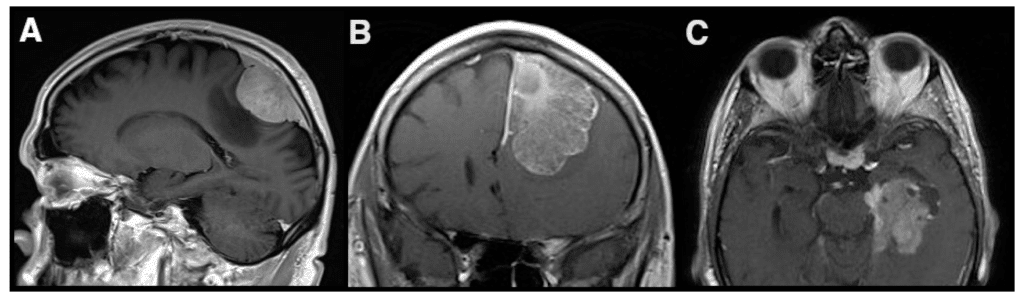

One of the key advancements in meningioma research lies in the development of diagnostic techniques. The diagnosis of meningioma usually involves a combination of imaging studies and histopathological examination. Non-invasive techniques like magnetic resonance imaging (MRI) and computed tomography (CT) scans have become invaluable tools in detecting and characterizing meningiomas. These imaging techniques allow healthcare professionals to visualize the tumor’s location, size, and surrounding structures, aiding in treatment planning.

Imaging Techniques

In addition to their diagnostic capabilities, imaging techniques have also advanced in terms of treatment monitoring and surveillance of meningiomas. With the development of functional imaging modalities like positron emission tomography (PET) scans, doctors can assess the metabolic activity of meningiomas, which can serve as a marker for tumor aggressiveness. Additionally, advanced imaging techniques, such as perfusion imaging and diffusion tensor imaging, provide valuable information about blood flow and tissue organization within and around the tumor, aiding in treatment planning and assessing treatment response.